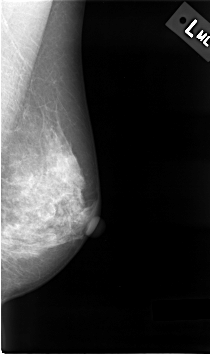

C_0015_1.LEFT_MLO

LEFT_MLO LINES 4632 PIXELS_PER_LINE 2728 BITS_PER_PIXEL 12 RESOLUTION 50 NON_OVERLAY